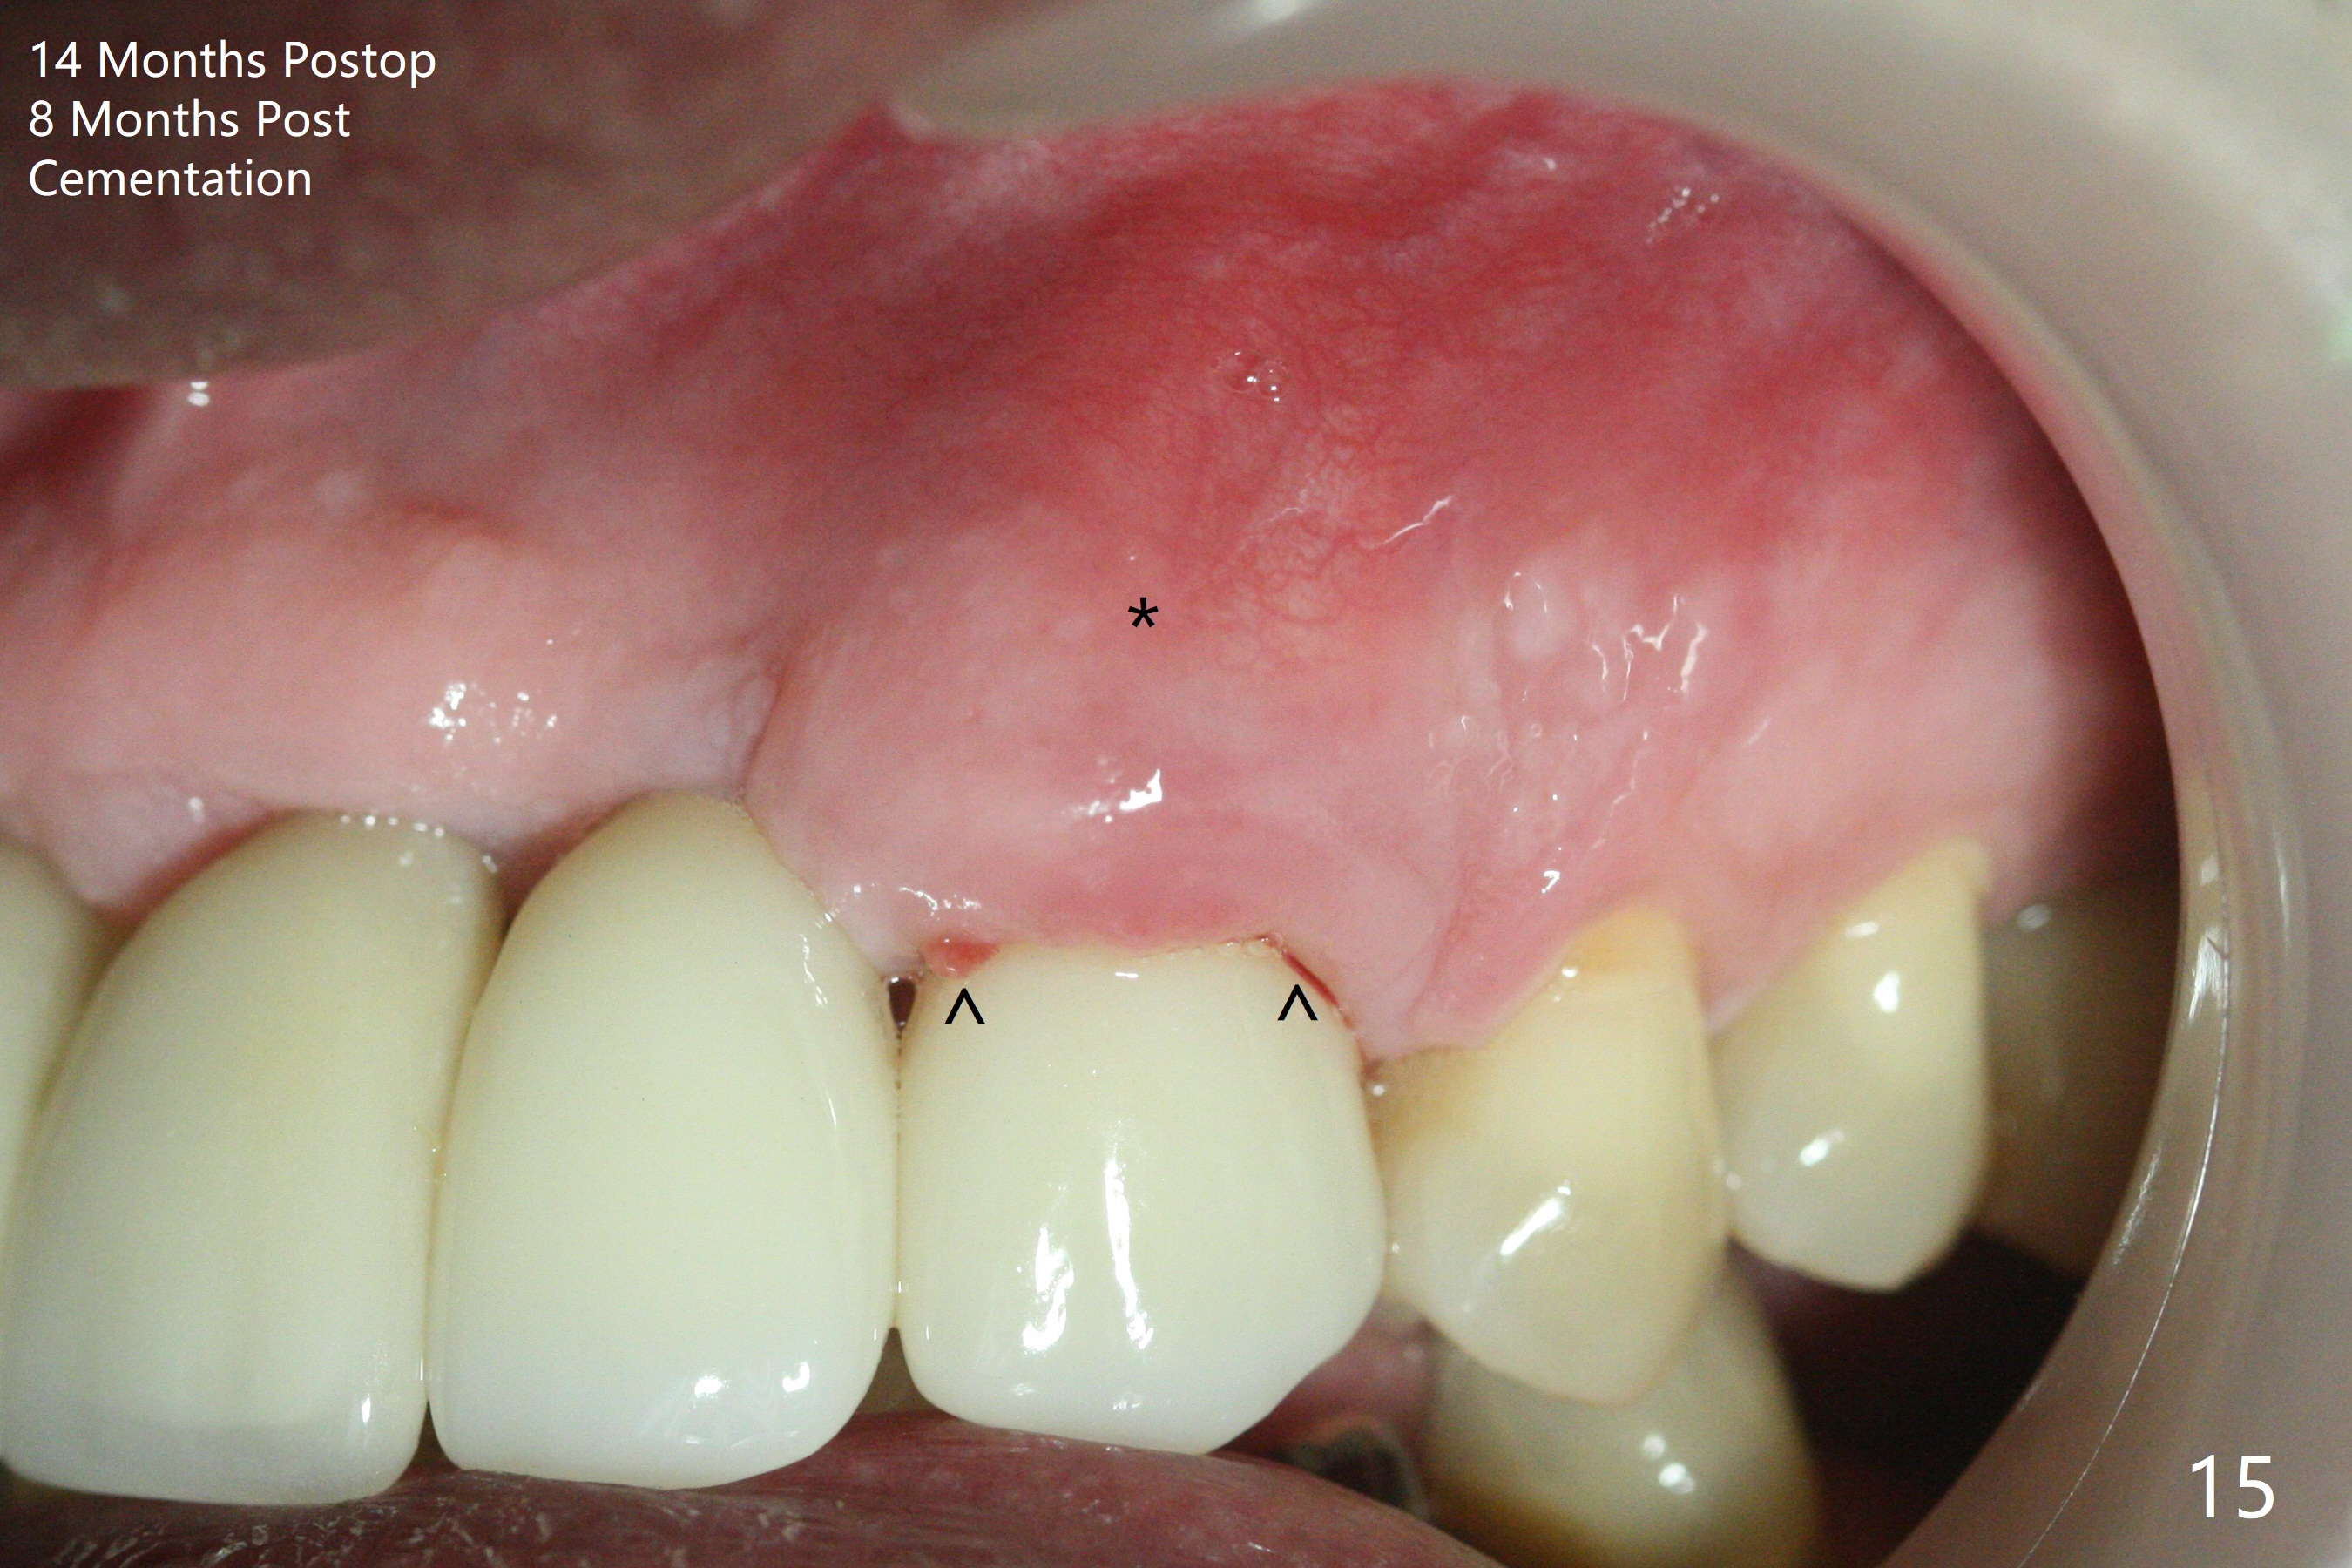

The buccal plate at #10 undergoes atrophy 9 months post immediate implant (Fig.1 *). To prevent the same post-extraction complication at #11, a technique called socket shield is going to be adopted. The buccal portion of the root (Fig.2-6 R, half-moon shaped) remains in place while a 3.5x13 mm implant is placed in the palatal portion of the socket (>50 Ncm). In fact the root is trimmed slightly subcrestal (Fig.6 C). It is assumed that there will be no or minimal bone resorption as long as the periosteum between the buccal plate and the remaining buccal root is not disturbed after tooth removal. After placement of a 4.5x15 degrees A (2mm) angled abutment and Vanilla graft (Fig.7 *), an immediate provisional is fabricated (using a central incisor crown form for #10 because of extra wide space of #11, Fig.8). There is no buccal plate atrophy at the canine 11 days postop (Fig.9). There is smooth transition from the grafted bone to the native bone 4.5 months postop (Fig.10). The buccal plate remains non-atrophic at the canine 4.5 months postop (Fig.11,12). CT taken 1 month post cementation shows that the implants at #10 and 11 are placed somewhat lingually (Fig.13,14 L (*: socket shield)). Gingival swelling is noted (Fig.15 *) with +Bleeding On Probing (^) 8 months post cementation (at the time of #21/24 impression). It appears that the socket shield (Fig.16 S) causes infection and loss of bone graft (*). The shield will be removed with an oblique accessory incision to save the papilla between #10 and 11 (Fig.17 black line). Prepare PRF for sticky bone (x1).